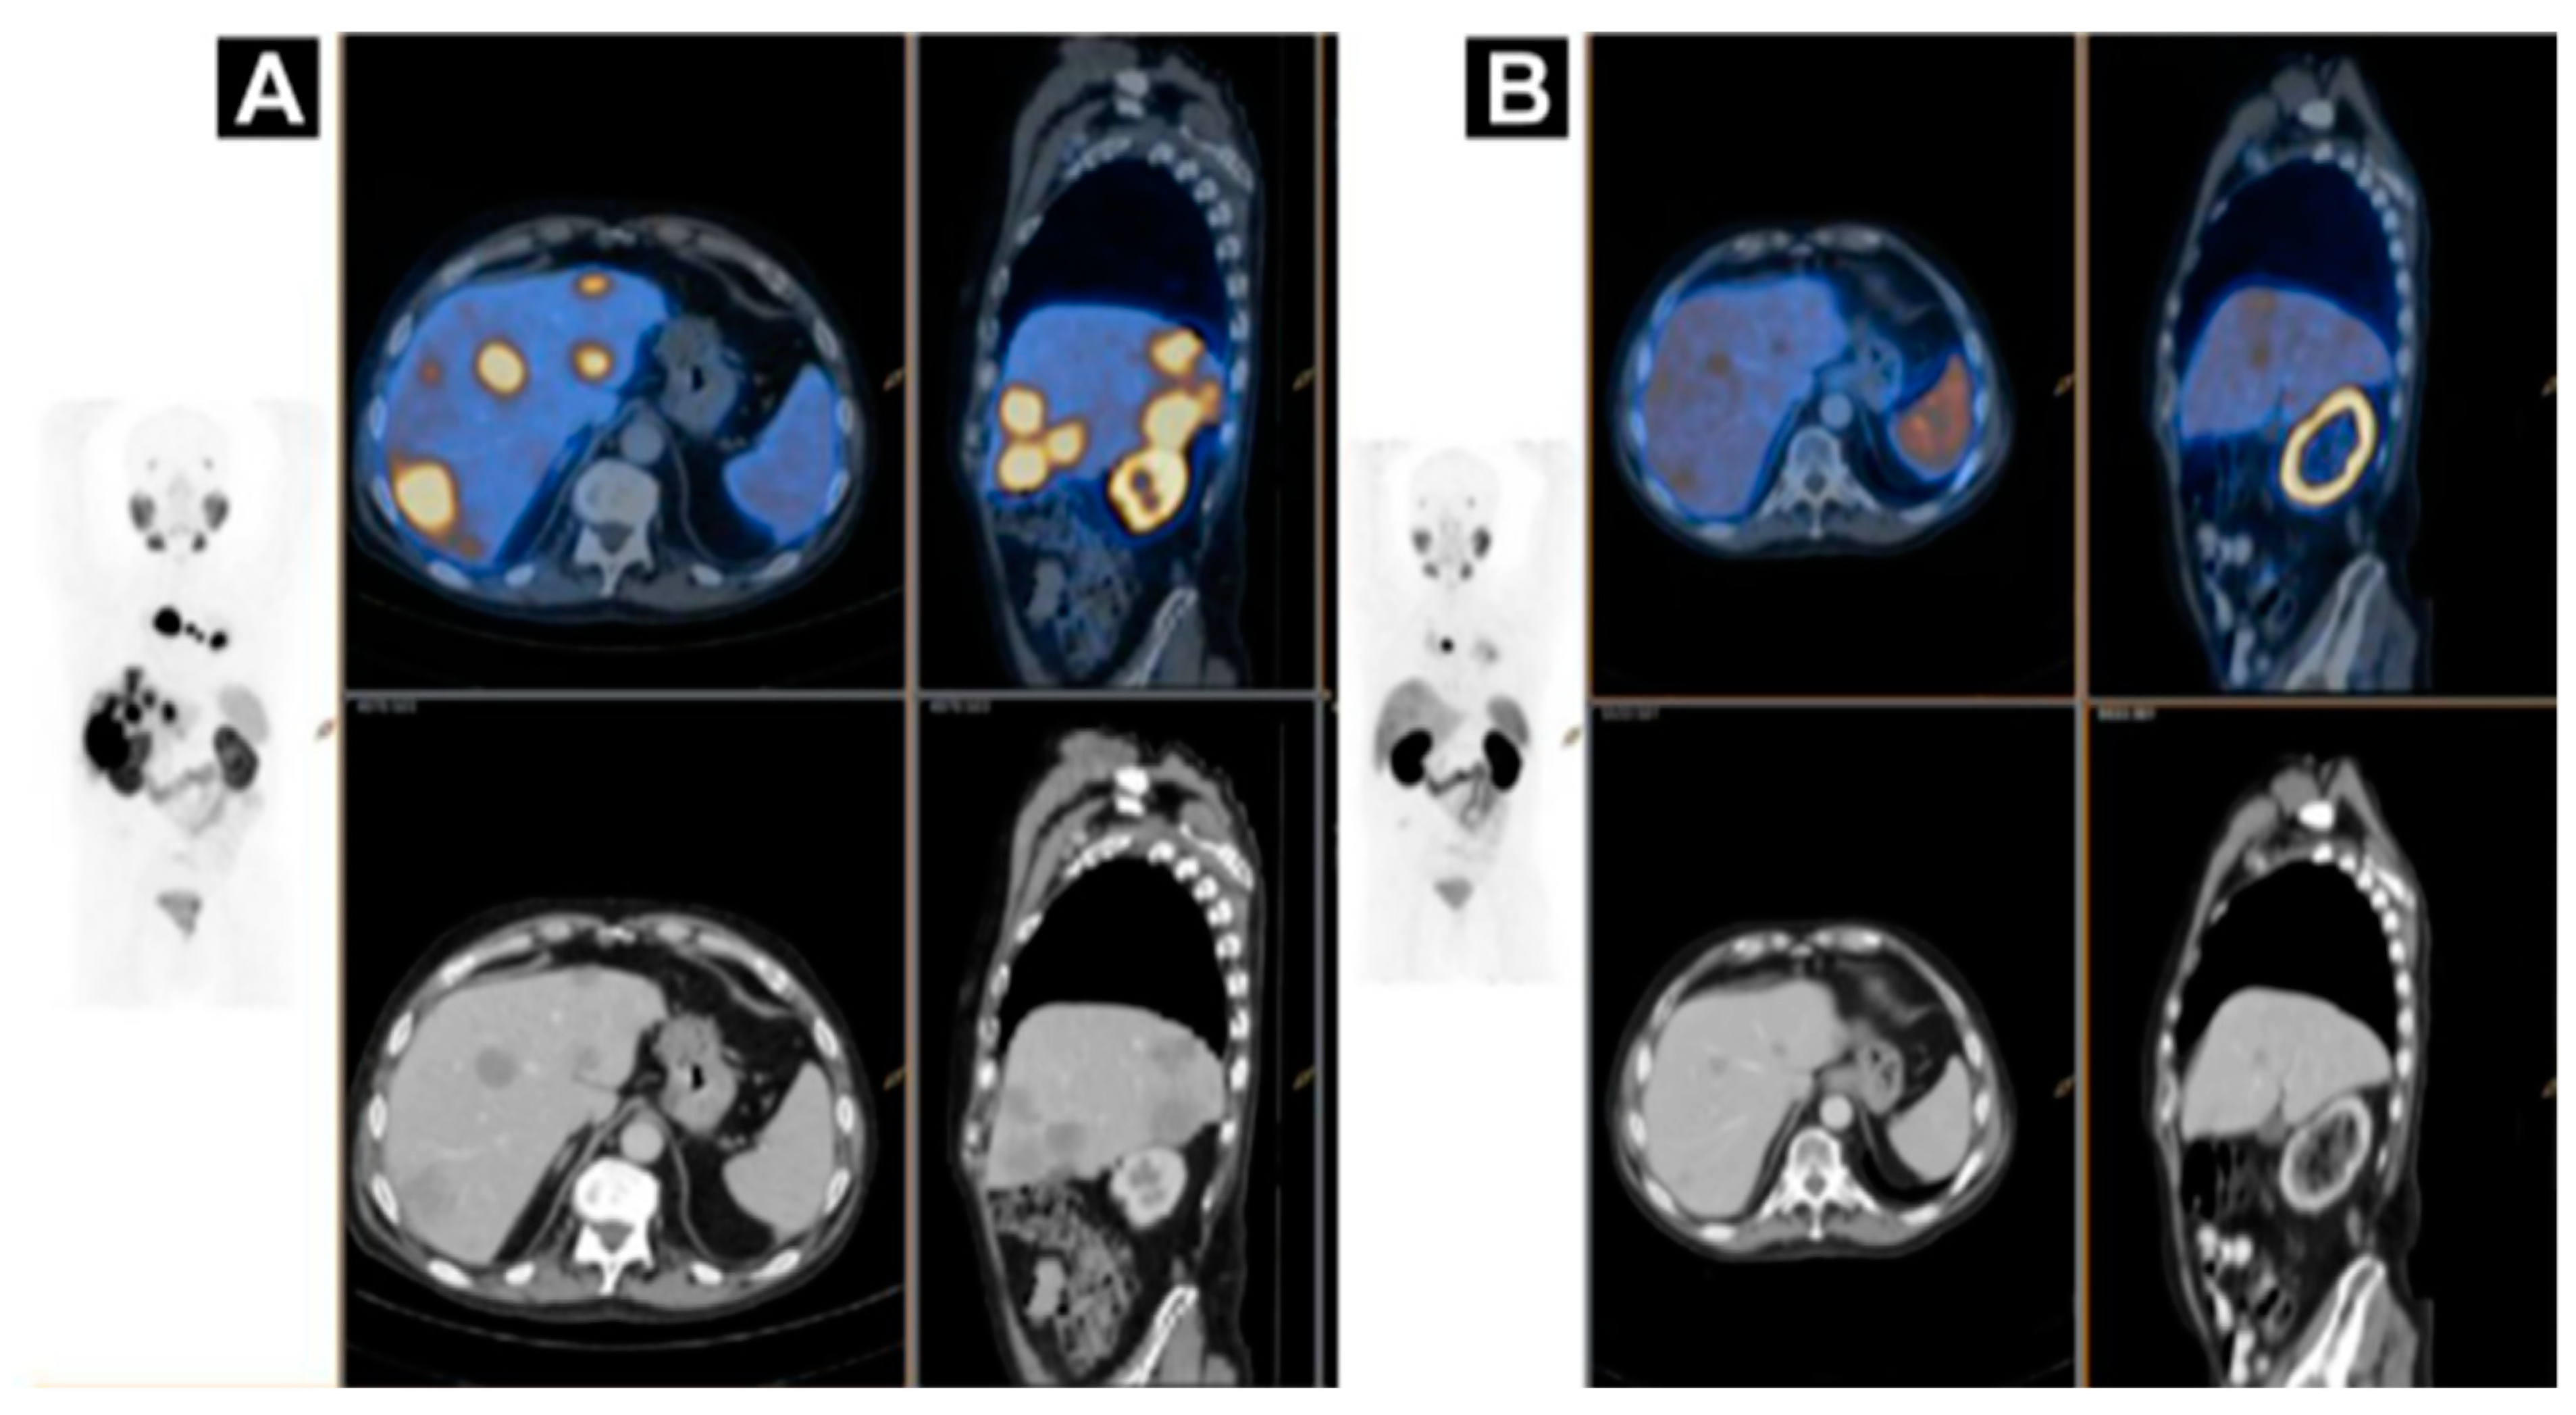

Figure 8.

A case of homogenous treatment response (A) [68Ga]Ga-HBEDD PSMA-11/PET-CT: Highly PSMA-avid liver and mediastinal lymph nodal metastases (SUVmax 70) on screening (PSA 340 ng/mL). (B) [68Ga]Ga-HBEDD PSMA-11/PET-CT: 3 months after 4 cycles of [177Lu]Lu-PSMA therapy (PSA 1.5 ng/mL) exhibited marked biomarker and RECIST response with minimal residual PSMA activity in liver metastases and solitary PSMA-avid mediastinal lymph node. Reproduced from [146].